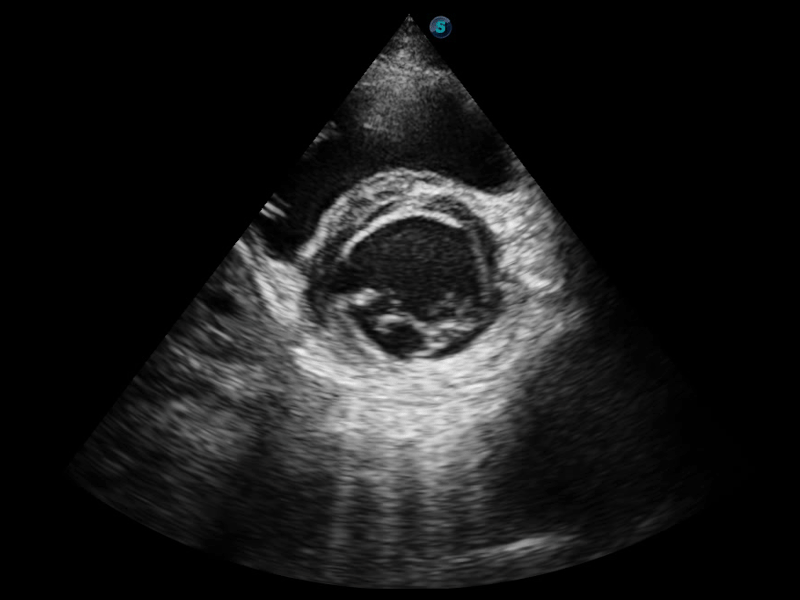

開立醫(yī)療通過不斷的技術(shù)創(chuàng)新,為大眾的生命健康提供持續(xù)關(guān)愛。P12 Plus采用全新一代超聲成像平臺,新平臺旨在將真實(shí)還原組織解剖結(jié)構(gòu)作為首要目標(biāo)。平臺采用全新集成化硬件模塊,搭載新一代芯片,系統(tǒng)性能得到大幅提升,為您的診斷提供了豐富的臨床信息。優(yōu)異的圖像表現(xiàn),豐富的探頭配置,全面的應(yīng)用功能,為您日常診斷提供了可靠的助手。

P12 Plus

彩色多普勒超聲診斷系統(tǒng)